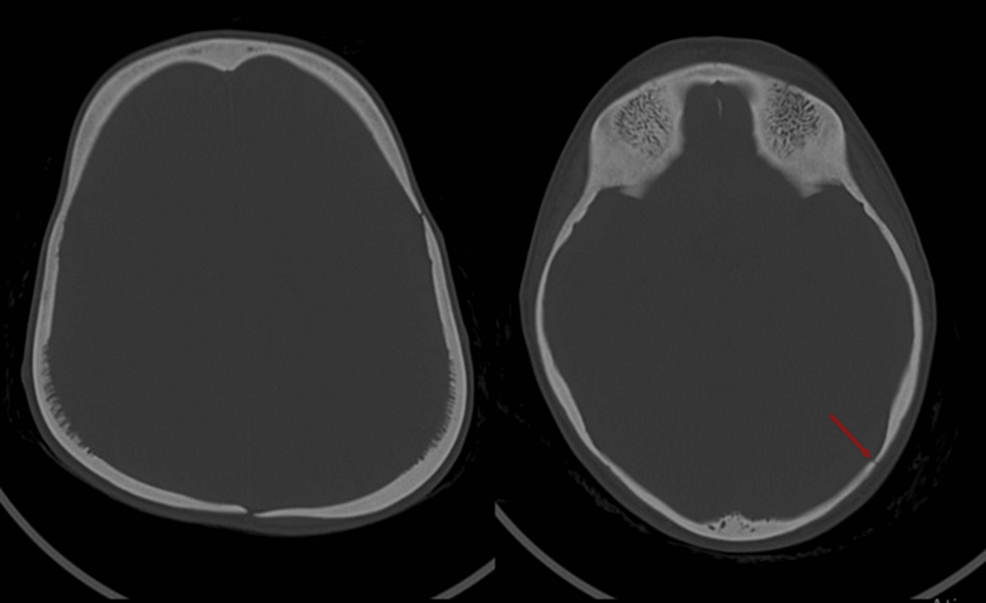

• Head Trauma in Pycnodysostosis: An Imagiological Challenge

Head Trauma in Pycnodysostosis: An Imagiological Challenge